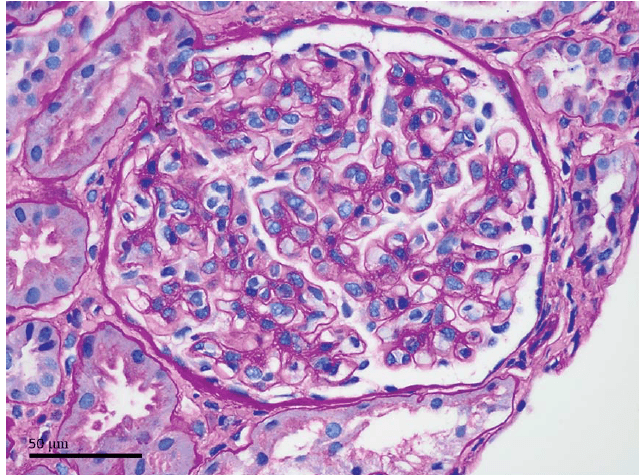

Foi iniciado amiloride 10mg/dia, sendo observado normalização dos níveis de potássio e magnésio. Não ocorreu melhora da TFGe, sendo atribuído a um quadro de possível nefrite tubulointesticial secundário hipocalemia crônica.